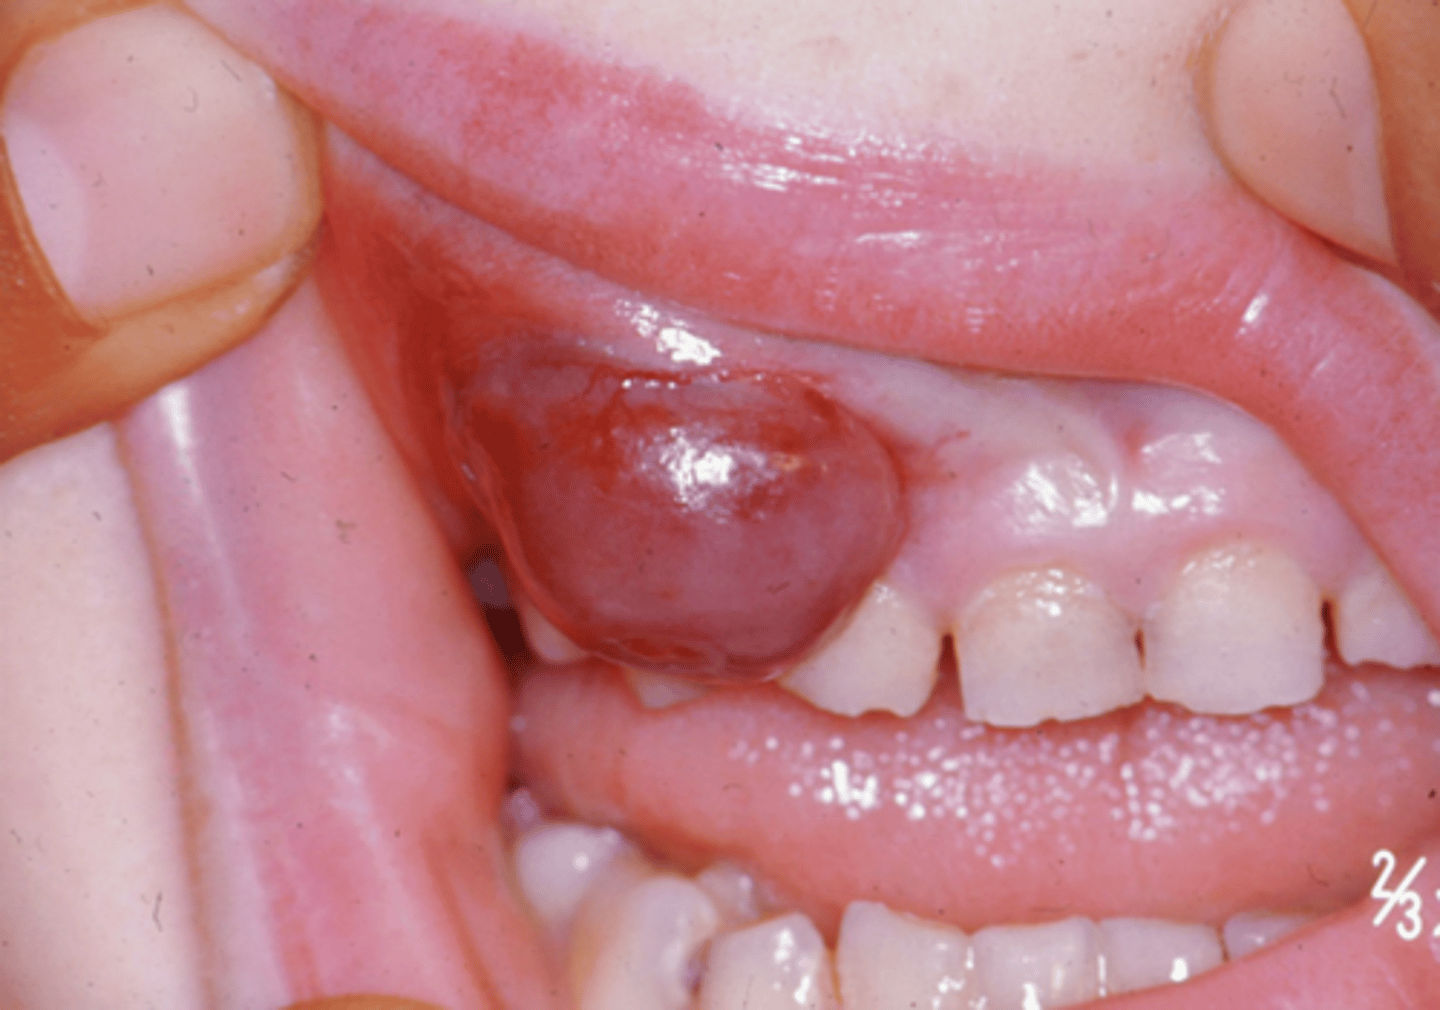

what is a peripheral giant cell granuloma?

large reddish/purple benign lesion that contain multinucleated giant cells and fibroblasts